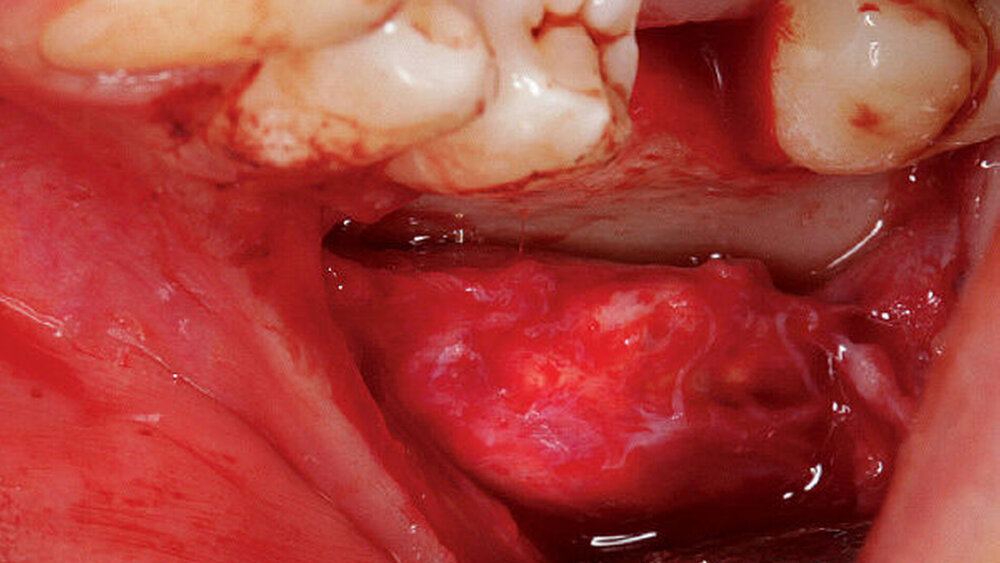

Auch radiologisch ließen sich keine Auffälligkeiten darstellen (Abbildung 1). Aufgrund der lang anhaltenden Persistenz und auf Wunsch der Patientin entschieden wir uns für eine chirurgische Inspektion mit Option auf Entfernung des Tumors. Analog zur Schnittführung der Weisheitszahnentfernung wurde das Gewebe Regio 36 marginal mit einer mesialen und distalen Entlastung eröffnet und ein Spaltlappen gebildet. Bis zur verdächtigen Raumforderung wurde stumpf mit der Schere präpariert (Abbildung 2), wobei sich die Läsion schließlich als abgekapselte Struktur darstellte, die sich sehr gut aus dem umliegenden Gewebe entfernen ließ. Das klinische Erscheinungsbild der Raumforderung entsprach am ehesten der eines Lipoms (Abbildung 3). Nach kompletter Entfernung der Raumforderung (Abbildung 4) wurde die Wunde mit Nähten speicheldicht verschlossen (Abbildung 5).